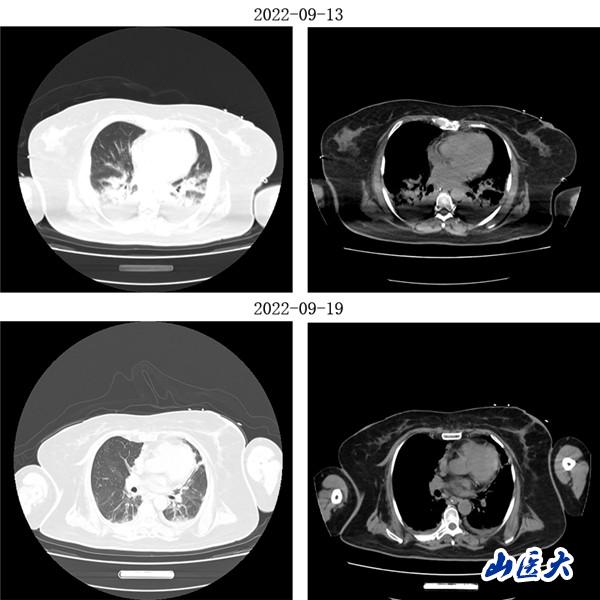

重癥醫學科三病區張文凱主任團隊深入分析了兩位患者的病情。考慮到兩名老年患者均已出現急性呼吸窘迫綜合征,決定采用俯臥位通氣技術為他們治療。在張文凱主任的指導下,侯林義主治醫師帶領張承、孫潔住院醫師對女性患者經俯臥位通氣治療,92小時后復查胸部CT,雙肺明顯好轉,氧合指數由90上升至300mmHg以上,吸氧濃度由100%降至35%,ARDS明顯改善;對男性患者,采用聯合持續性血液濾過(CRRT)治療方案,經俯臥位通氣治療66小時后復查胸部CT,顯示明顯改善,同時氧合指數由102上升至360mmHg左右,吸氧濃度需求下降至40%,全身水腫情況也明顯減退。

(女性患者治療前后胸部CT對比)